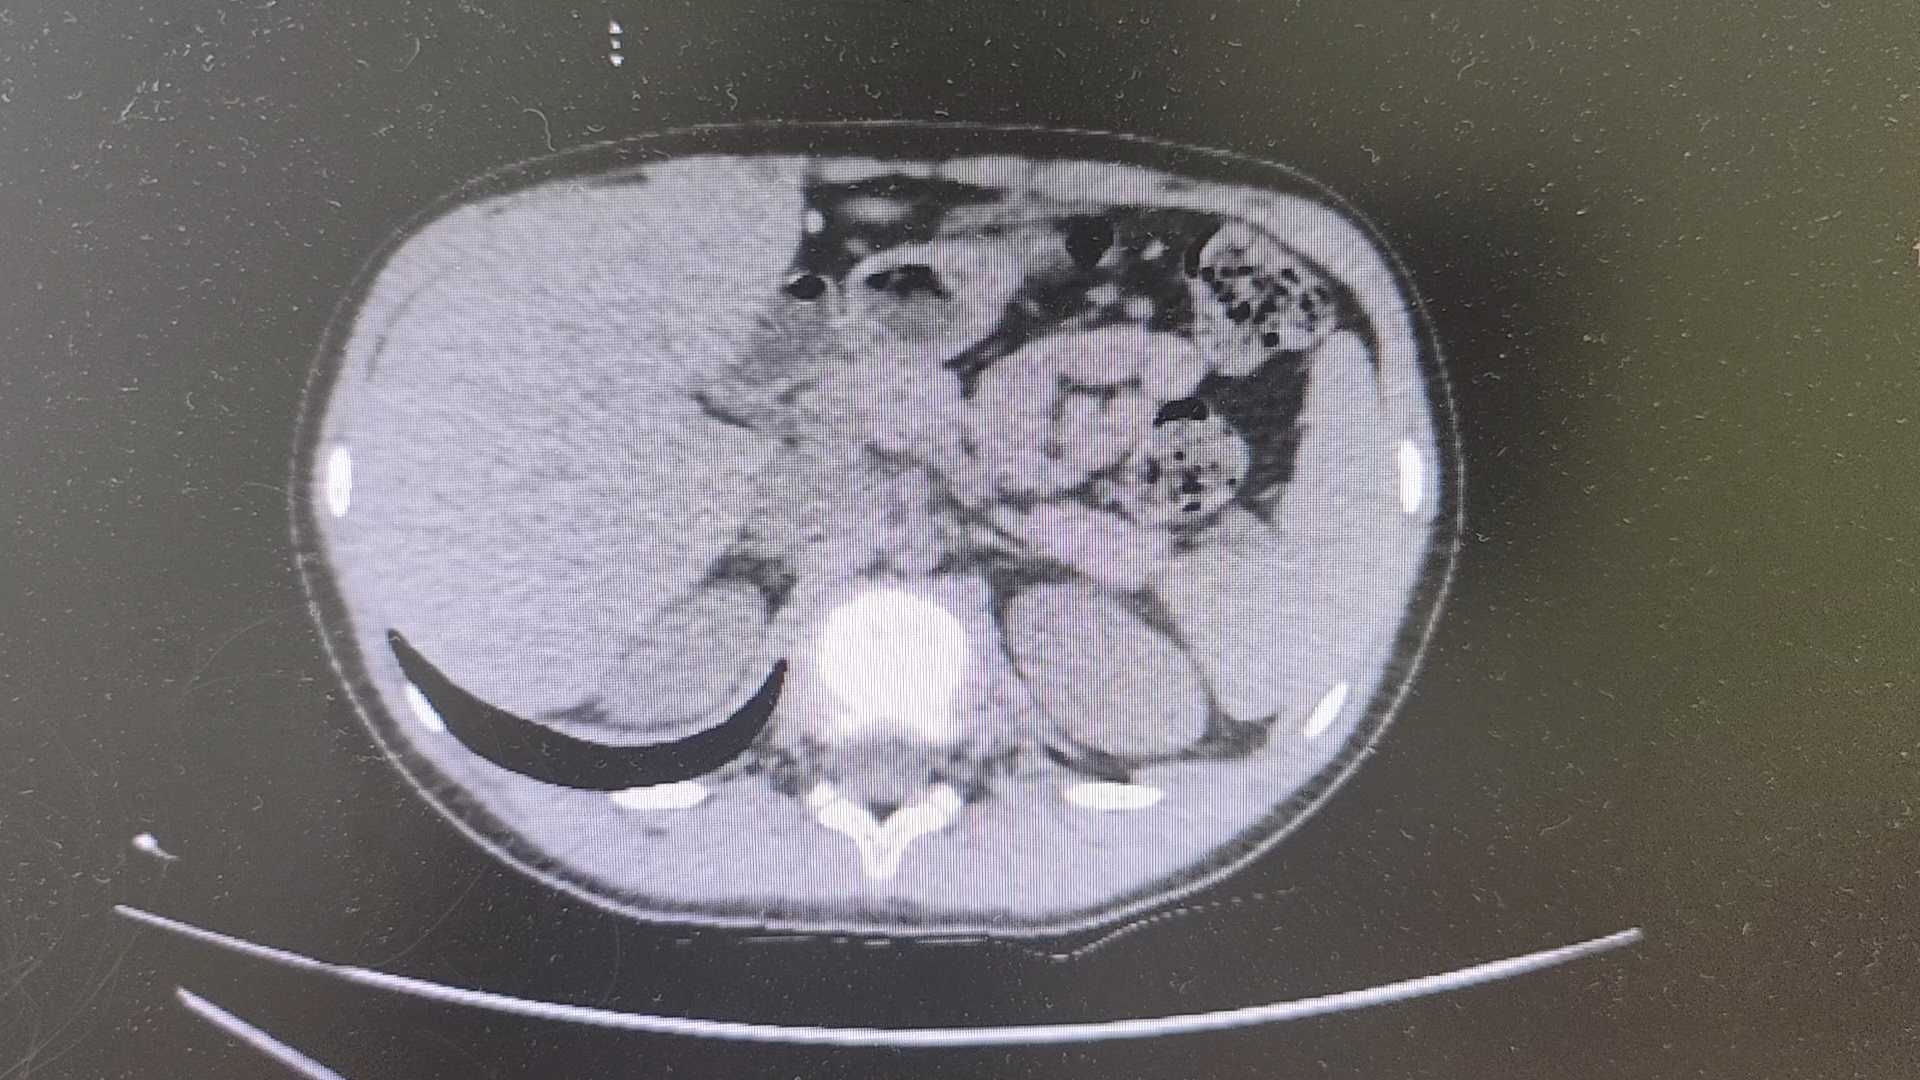

【检查】:

【临床诊断】:1.消化道出血,美克尔憩室?2.中度贫血3.腹腔积液

【治疗经过及结果】:转科后完善术前准备,行腹腔镜探查,距离回盲部40cm处末端回肠系膜缘呈憩室样盲端,伴行正常回肠肠管约5cm,根部与回肠肠腔连通。